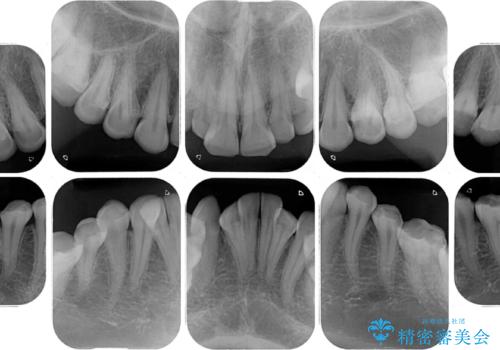

- 一時期の拒食症に伴い歯が酸で溶けてボロボロになってしまったとのことで来院された患者様です。

酸によりエナメル質の大半が溶けており、下顎前歯以外は酷いむし歯のような状態でした。

当初はほとんどの歯をむし歯治療のようにオールセラミッククラウンにて補綴治療を行う予定でしたが、仮歯に置き換えた時点で、口元の突出感や下顎前歯の叢生が気になるとのことで、上下左右の第一小臼歯4本を抜歯したワイヤー装置での抜歯矯正を行うこととしました。

矯正治療終了後に、残った歯をオールセラミッククラウンにて補綴治療を行うこととしました。